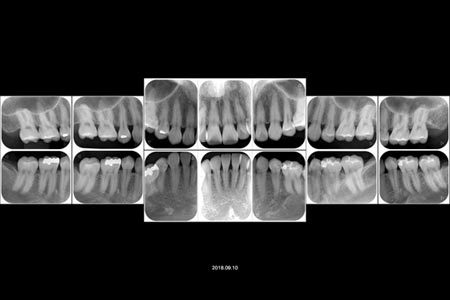

デンタル 詳細なレントゲン写真 10枚法のススメ 15 0929 夜21時迄平間駅徒歩30秒ワコ歯科 矯正歯科 川崎中原区